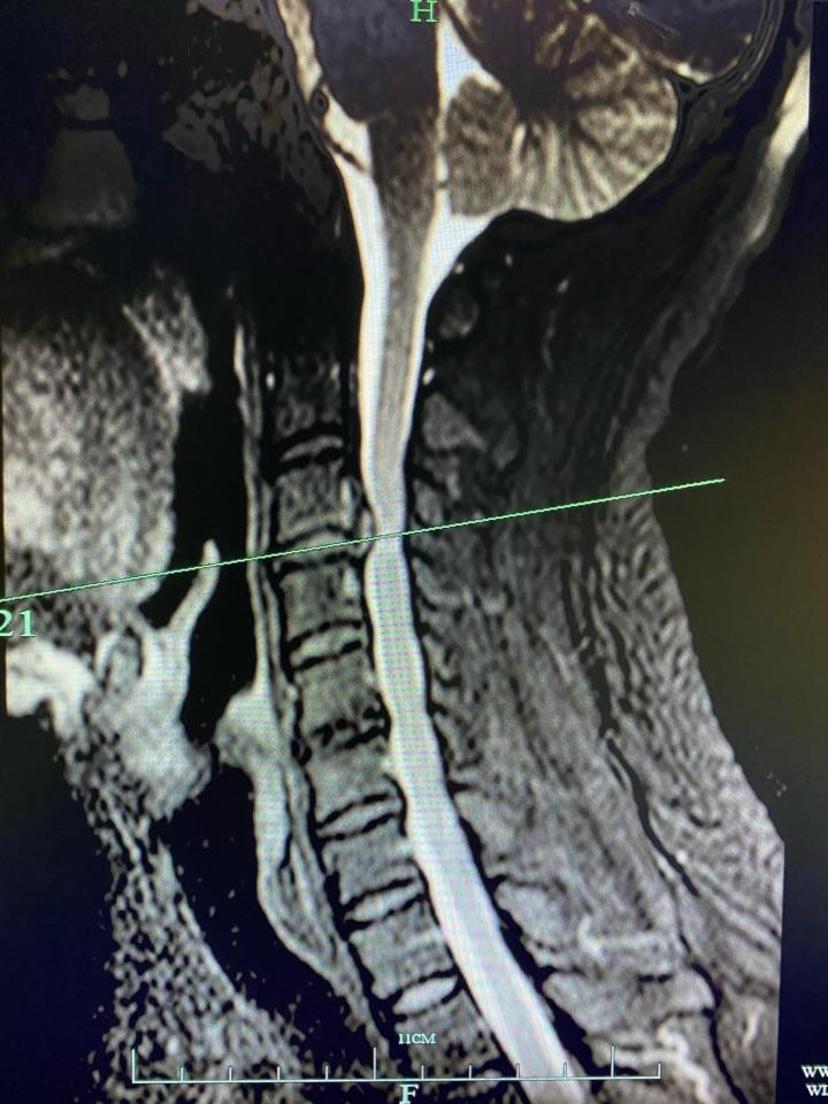

患者,男,30多岁,四肢麻木有7年了,进行性加重,一直没能明确诊断,近两个月来走路很吃力,双下肢紧绷感,走路摇摇晃晃,一不小心就摔跤,就诊我门诊后经磁共振检查示:高位颈椎病(颈3-4椎间盘突出、脊髓严重受压变细、脊髓变性),采用前路ACDF微创术式,术程1小时、出血约20ml、切口长约2.5cm,术后第一天感觉到双手轻松了很多,术后第二天正常下地走路,对比了术前术后走路的感觉,明显感觉到腿脚利索有力了,走路较术前稳当很多,术后第三天出院。温馨提醒:脊髓损伤严重、脊髓变性大部分是不可逆的,颈椎病发展到踩棉花感、走路不稳等情况请尽早就医,以免耽误病情。颈椎磁共振示:高位颈椎间盘突出,脊髓受压严重,脊髓变性

颈椎磁共振平扫示:脊髓神经受压严重,颈椎管狭窄